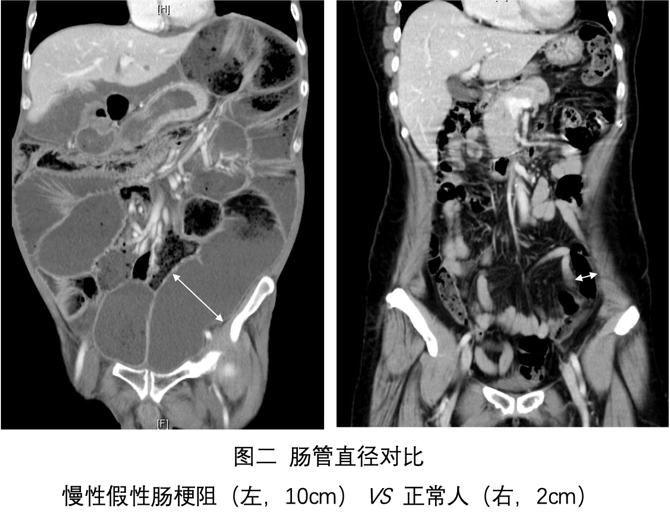

肠梗阻是指肠内容物无法正常通过肠道,导致患者腹胀、腹痛、呕吐、排便、排气停止。该病病因众多,假性肠梗阻是其中一种罕见类型。该病具有典型肠梗阻临床表现(图一、二),病变在肠壁本身(肠壁神经、肌肉和间质),肠腔并无机械性梗阻。病程超过6个月称为慢性假性肠梗阻。

临床表现为典型肠梗阻症状,并无特异性。肠动力差导致肠道细菌过度增殖,引起营养吸收不良、脂肪泻、体重下降及维生素缺乏,甚至引发营养相关并发症。部分病例出现泌尿系统症状。此病误诊率极高,多数患者发病到确诊平均需要8年,88%患者平均接收3次的手术(图三),就诊时病情处于晚期。